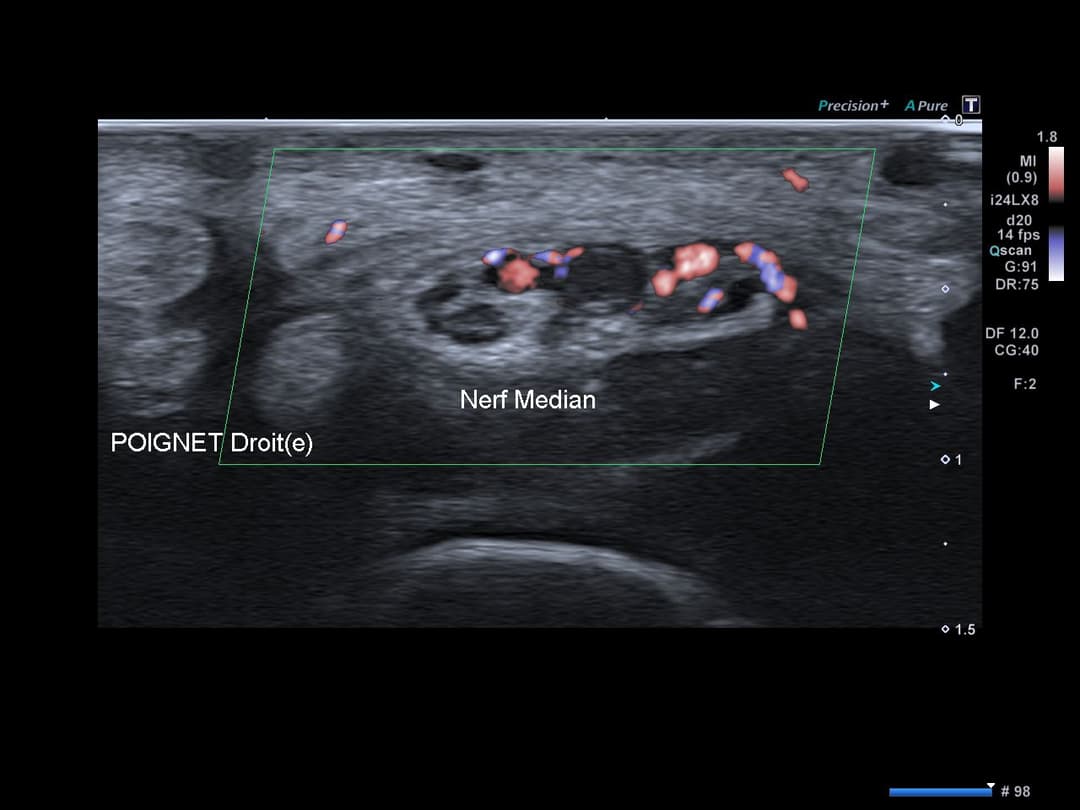

Matériel échogène endoluminale de l'artère médiane persistante du poignet droit, au niveau de son passage dans le canal carpien, traduisant une thrombose artérielle.

Accentuation de l'échogénicité des parties molles adjacentes traduisant un œdème réactionnel avec hyperhémie en Doppler couleur.

Nerf médian bifide de calibre additionnel dans les normes sans renflement notable.